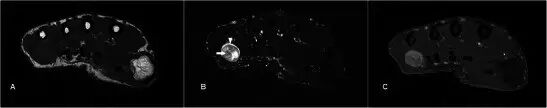

腱鞘囊肿Ganglion cyst 腱鞘囊肿是手部和手腕区域中最常见的肿块[2]。他们往往发生在年轻的成年人,女性发病更加频繁。它们被认为代表由慢性刺激引起的结缔组织的退化[3]。最常见的位置是在手腕的舟月关节背部。较不典型的部位包括手腕的掌侧从桡骨-舟骨( radio-scaphoid )或舟骨-大多角骨(scapho-trapezial)关节,在相对于掌指关节,以屈肌腱和远端指间关节[4]。MR显示了流体信号的良好外切的单个或多腔的损伤,但是信号可以根据蛋白质含量的量而变化(图1)。可以看到囊的轻度边缘增强,但是通常没有内部内容物的增强。鉴别诊断包括滑膜囊肿和其他囊性病变,例如表皮囊肿。

图1.24岁的女性腱鞘囊肿,呈现一个缓慢成长,坚定,无痛的手肿大约6个月。 (a)T1w序列显示在均匀低信号的大鱼际肌组织内的平滑、良好边缘病变。 (b)T2w-FS序列上的病变是高信号的。 没有看到侵入相邻结构。 (c)有最小的边缘增强,没有显着的内部增强(箭头)